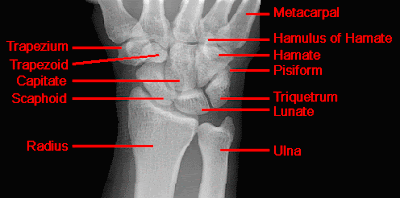

The Lisfranc joint is composed of 5 TMT joints in which the first through third MTs articulate with their corresponding medial, middle, and lateral cuneiforms. The fourth and fifth MTs articulate with the cuboid. The Lisfranc joint can be functionally divided longitudinally into the first ray, or medial column; the middle column, consisting of the second and third TMT joints; and the lateral column, consisting of the fourth and fifth TMT joints. A transverse line through these joints is not straight but highlights a recess, termed the keystone (similar to a Roman arch), formed by the second TMT joint. This joint lies approximately 1 cm proximal to the first TMT joint line and 0.5 cm proximal to the third TMT joint line.The joints are bound by thick plantar ligaments that form an interlocking pattern between the tarsal and lesser MT bones 2-5. These are reinforced by attachments of the posterior tibialis tendon. The first TMT joint also has strong plantar ligaments across the joint; these are reinforced by the attachment of the peroneus longus and anterior tibialis tendons. Also present between the lesser MTs is a series of intermetatarsal ligaments, which force the group to function more as a unit. No intermetatarsal ligaments exist between the first and second MTs, which is why they often exhibit divergent behavior. The weaker dorsal ligaments explain the majority of dorsal dislocations.11

The Lisfranc ligament originates from the plantar lateral aspect of the medial cuneiform and attaches to the plantar medial aspect of the second MT base. It is the thickest of the ligaments in this region, measuring up to 1 cm wide. This ligament provides the only soft-tissue link between the medial ray and the lesser MT and is responsible for this area's stability.